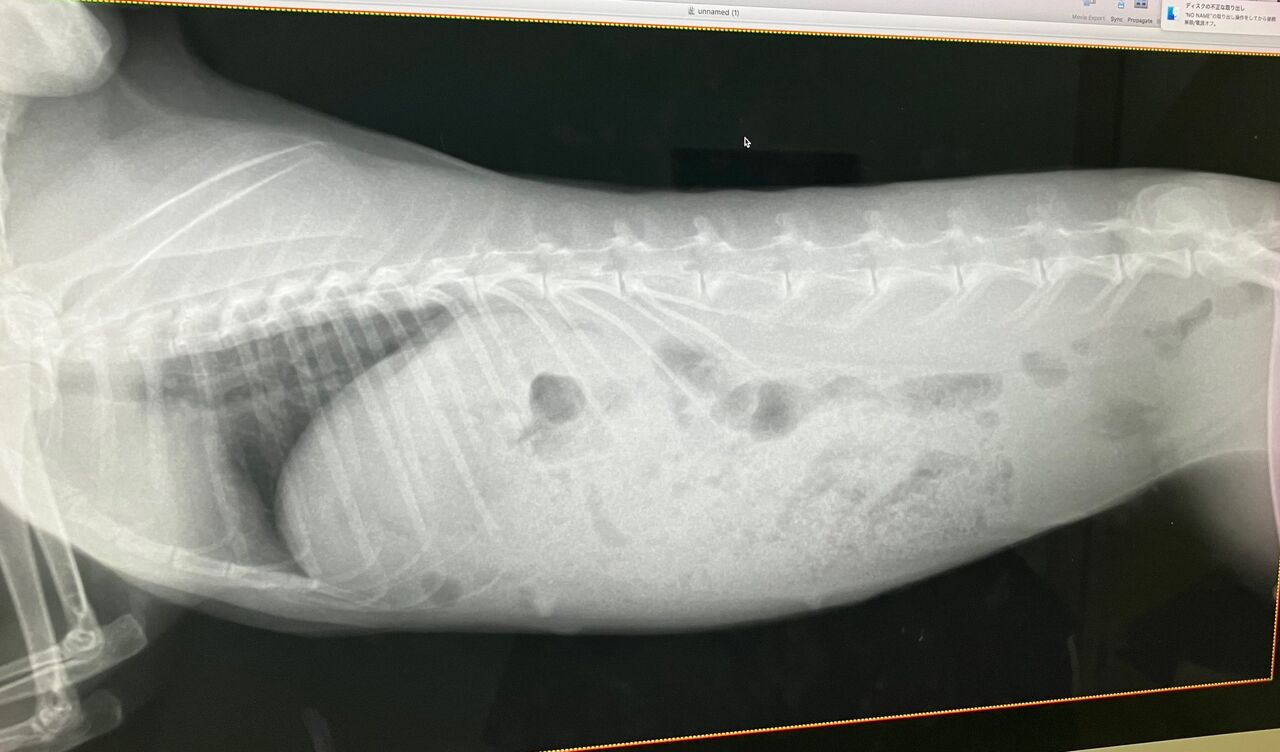

そして11月27日、避妊手術

術前の血液検査、レントゲン、特に問題ありませんでしたが、

口内検査で歯、奥歯右下3番目が少し内側に向いてたのでカット処置。